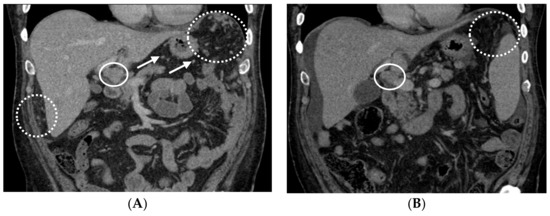

2.1. Patient #1

2.2. Patient #2